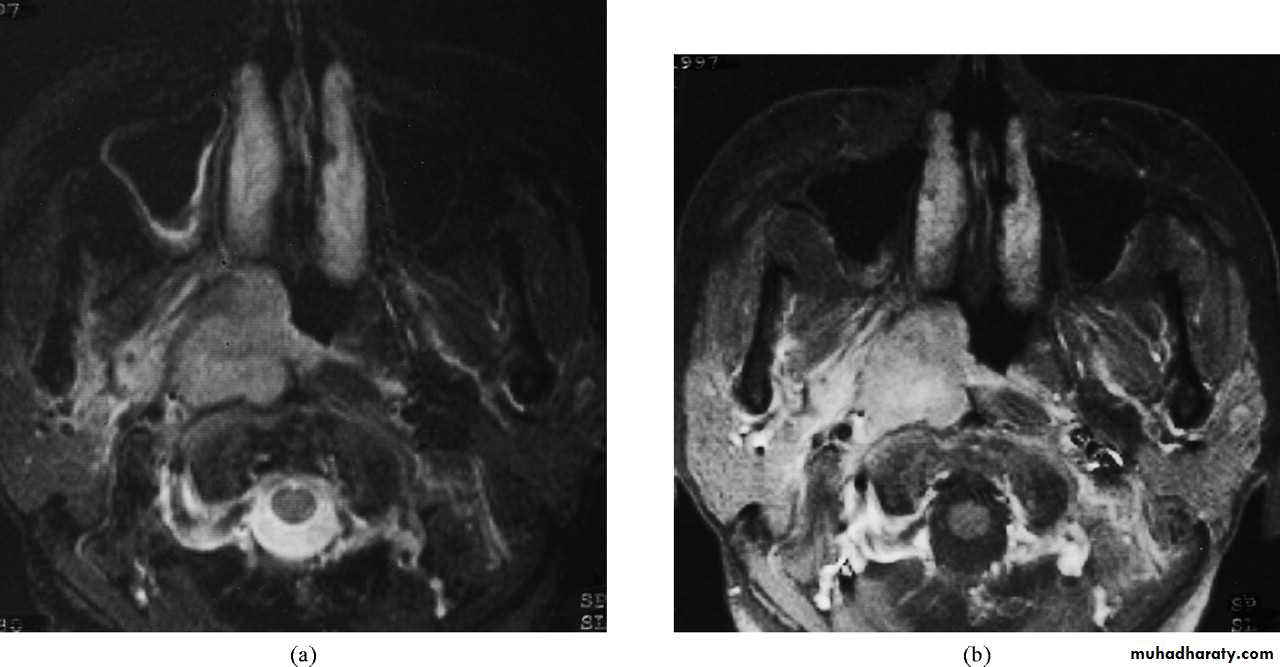

1. Imaging:a. X-ray of the base of the skull---- bony destruction involving the petrous bone, foramen lacerum and carotid canal.

b. CT scan and MRI: MRI is superior to CT scan in finding soft tissue involvement.